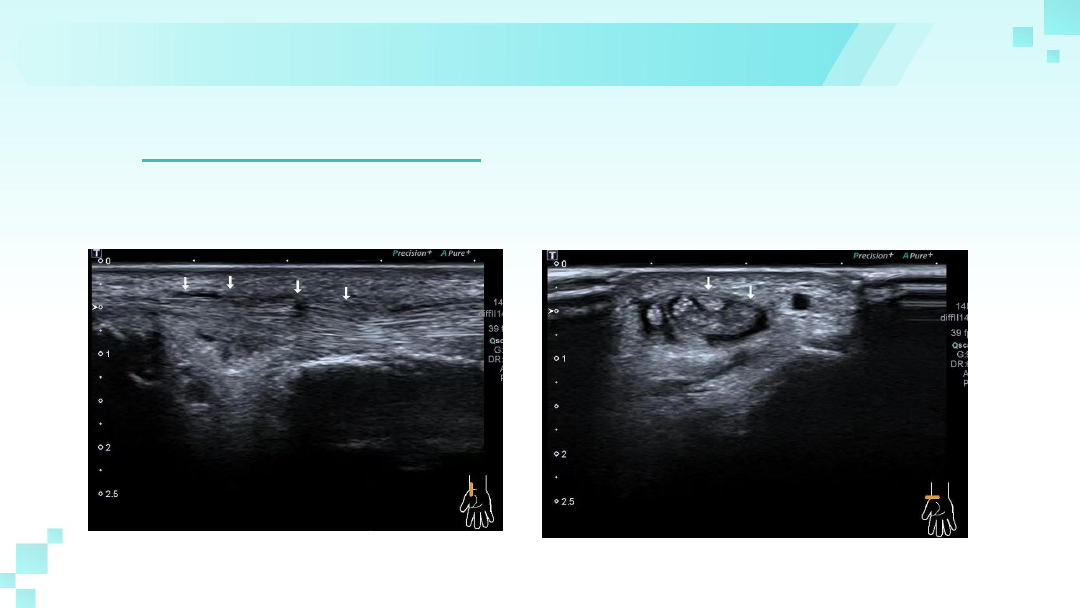

超声

1、腱鞘增厚:炎症导致腱鞘增厚(>1mm),

超声下呈现低回声。

2、肌腱肿胀:拇长展肌腱和拇短伸肌腱增粗,在横向扫查中显

示肌腱变圆,厚度可达同侧近心端2倍以上。注意第一伸肌室内

有无间隔及肌腱数量变异。